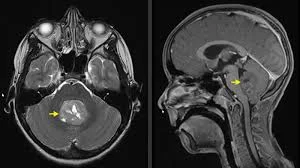

- Μαγνητική τομογραφία (MRI) εγκεφάλου με σκιαγραφικό – αναδεικνύει τη θέση, το μέγεθος και τα χαρακτηριστικά του όγκου (συχνά συμπαγής, ετερογενώς ενισχυόμενος, με πιθανές κύστεις ή αποτιτανώσεις).

- ΜRI όλης της σπονδυλικής στήλης πριν το χειρουργείο, για να ελεγχθεί αν υπάρχει διασπορά κατά μήκος του εγκεφαλονωτιαίου υγρού (οζίδια ή «πρόσληψη» των μηνίγγων).